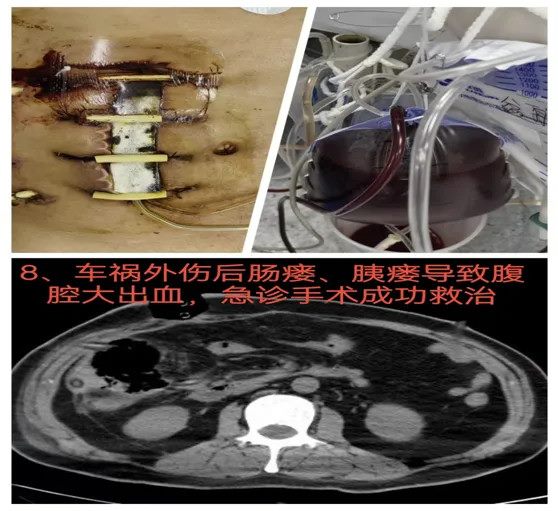

08结肠坏死结肠瘘、胰瘘合并腹腔大出血:紧急腹腔探查与多脏器支持

37岁男性患者在省外发生车祸,导致腹部大出血,并在当地急诊进行手术治疗。术后2周,患者切口愈合不良,伴随严重腹腔感染,疑似结肠瘘与胰瘘。因病情危重,患者转入郑大五附院继续治疗。入院时,患者腹腔大出血,血红蛋白下降至37g/L,生命体征极为不稳。经过多学科会诊和紧急评估,决定急诊进行腹腔探查,术中发现结肠肝区坏死,并伴有大量凝血块形成。最终决定进行结肠瘘切除及腹腔负压冲洗引流术。术后,患者的腹腔感染得到有效控制,血红蛋白逐渐恢复正常,感染明显好转。

难点总结:本病例的难点在于患者复杂的伤情与术后并发症,尤其是结肠坏死、结肠瘘、胰瘘和腹腔大出血的多重危机。患者病情严重,急诊手术中的决策需要迅速而精确,尤其是如何平衡多个问题的治疗。

推荐理由:通过及时的腹腔探查、结肠瘘切除及腹腔引流术,成功控制了出血并稳定了患者病情。该病例展示了在多脏器损伤和严重感染情况下,如何通过快速反应和精准手术进行有效干预,挽救了患者生命。